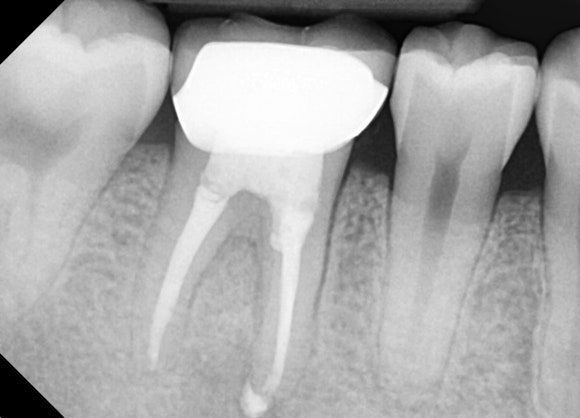

20241224

국가고시를 앞두고 있는 젊은 남성분입니다.

오른쪽 아래 신경치료를 하고 크라운을 씌운 치아가 있습니다.

문제 치아를 확대하는 엑스레이를 찍어보니

뿌리 주위로 기분 나쁜 검은 그림자가

드리운 것을 확인할 수 있습니다.